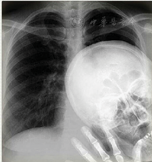

这些沉痛的代价让人了解到了X射线的另一个方面––"X射线的危害性",以至于早期就投入X射线研究的大发明家托马斯·爱迪生和他的助手麦迪逊(Clarence Madison Dally)以及米伦·卡萨宾(Mihran Kassabian)等长期从事X射线管实验工作,1990年后2人手部均患皮肤癌症。1903年,当记者问及爱迪生该"事件"真相时,爱迪生痛心地回答说,"别再跟我再谈X射线了……我怕它们………!!"。图10,图11,图12,图13是早期不正当使用X射线机的情况,其中图10为1903年医生在无任何防护条件下进行的胸部X射线透视的操作,该图床下的X射线管是4π立体角发射的无准直操作,医生也没有任何防护措施。图11是50年代在英国简易防护条件下进行的近距离透视操作,但医生有了铅手套和铅围裙等简单防护。在我国,这种透视操作直到80年代初期才禁止。图12是美国部队医院使用移动式床前X射线机为士兵做X射线检查留下的珍贵历史照片;图13是医生和护士用布带固定幼儿来拍摄X射线片的操作。